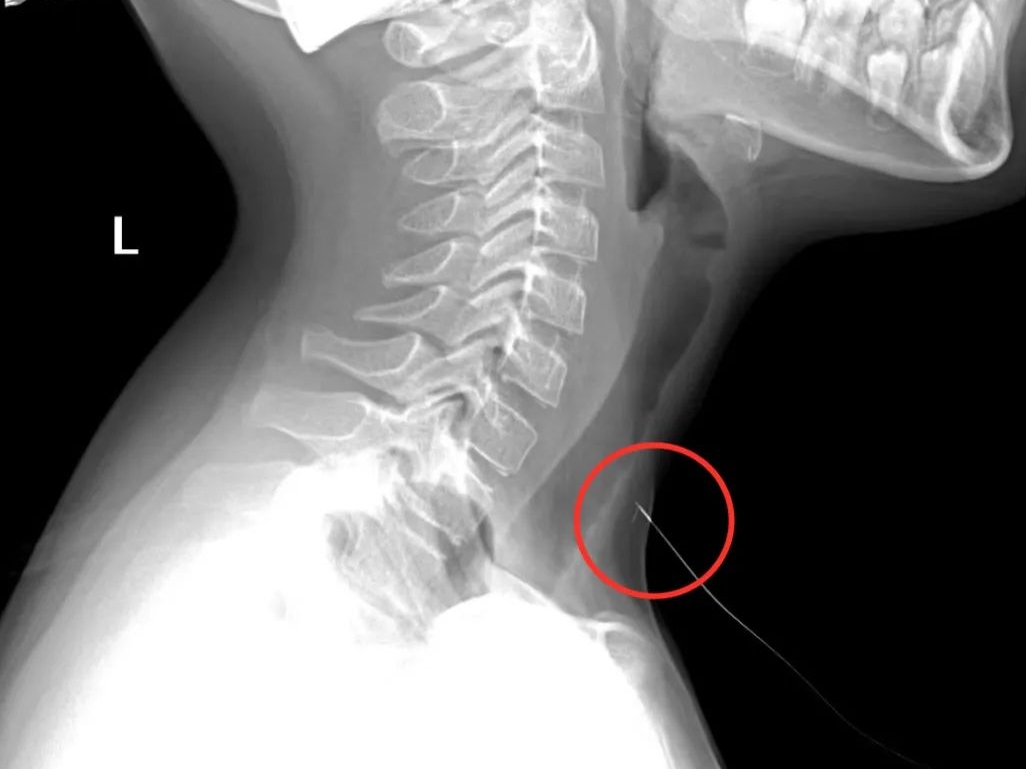

异物刺入孩子皮肤,家长不要自行拔除